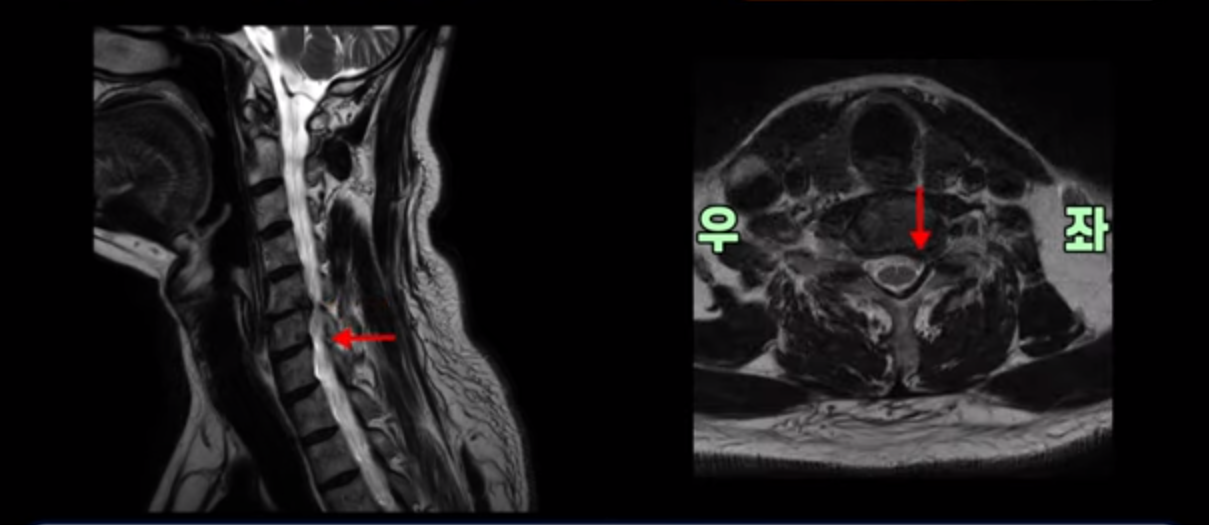

우선 이분 증상은 좌측 어깨와 팔 통증입니다. 이분 MRI를 보면 5번 6번과 6번 7번이 안 좋아 보입니다.

5번 6번에는 오른쪽과 왼쪽 모두 디스크 파열이 있고,

6번 7번에는 왼쪽으로 디스크가 밀려 나와 있습니다.

왼쪽으로 신경이 빠져나가는 추간공을 보면 보시다시피 5번 6번과 6번 7번 신경 구멍이 아래나 위에 비해 막혀있는 게 보입니다.

디스크도 밀려 나와 있고 협착도 있는 겁니다.